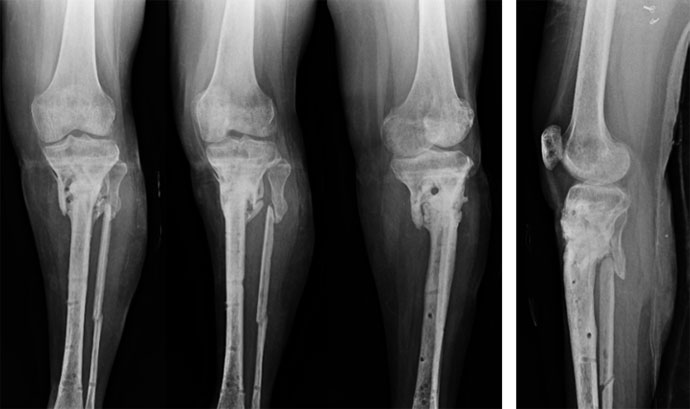

Pre Treatment

This 41 year old lay presented to us in 2008 with nonunion of left proximal tibia since 2001. This was a pretty difficult situation for her as she was diagnosed as a case of Multiple Myeloma. She was operated for the tumor in the tibia and thereafter several times for controlling infection and getting the fracture to unite. She was barely able to walk with support and on top of that was very much depressed.